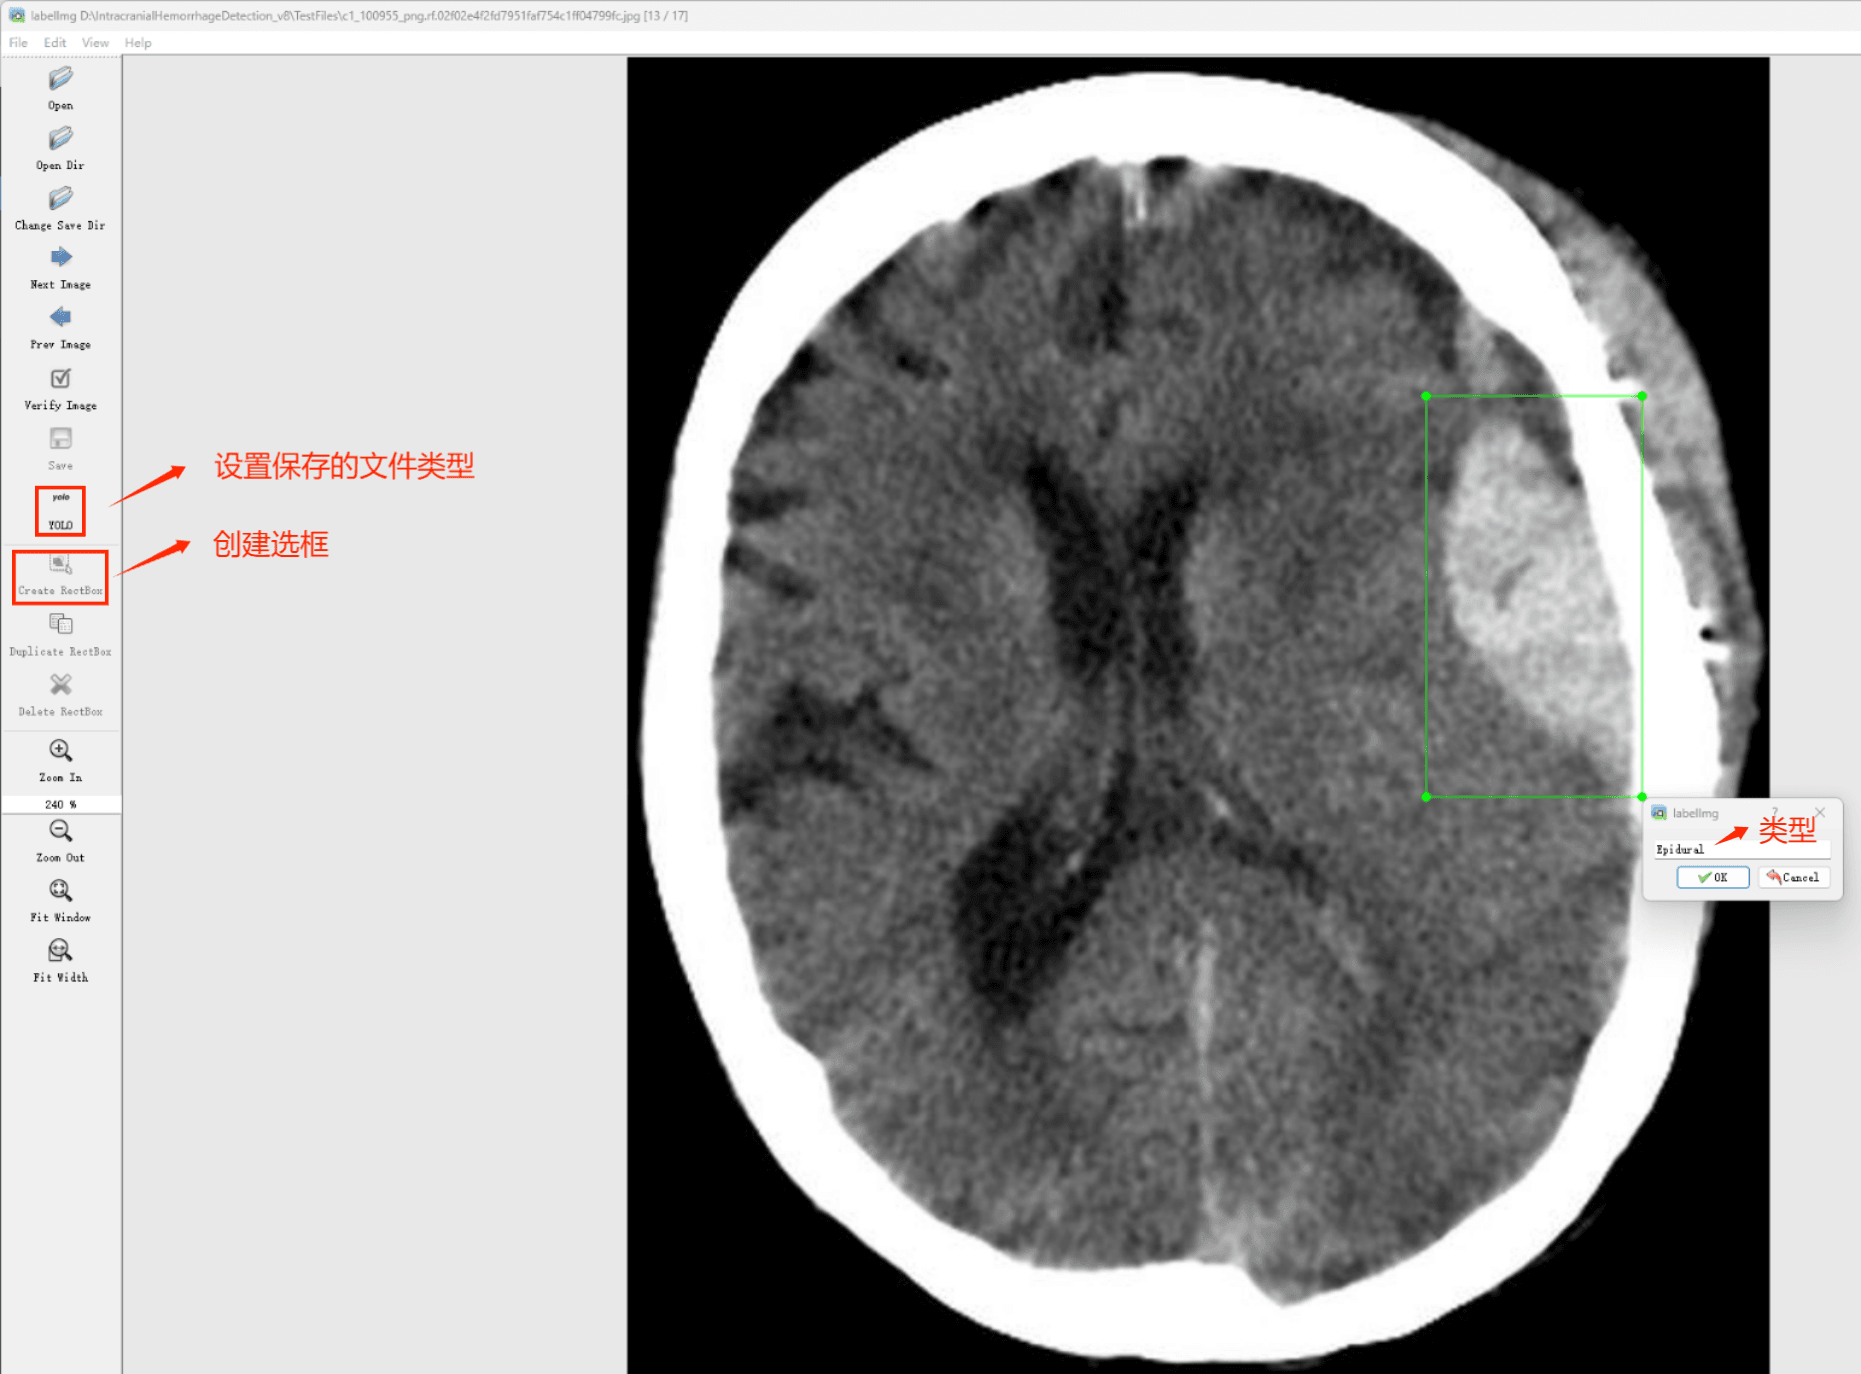

目标检测标注工具

(1)labelimg:开源的图像标注工具,标签可用于分类和目标检测,它是用python写的,并使用Qt作为其图形界面,简单好用(虽然是英文版的)。其注释以 PASCAL VOC格式保存为XML文件,这是ImageNet使用的格式。此外,它还支持 COCO数据集格式。

初识labelimg

打开后,我们自己设置一下

在View中勾选Auto Save mode

接下来我们打开需要标注的图片文件夹

并设置标注文件保存的目录(上图中的Change Save Dir)

接下来就开始标注,画框,标记目标的label,然后d切换到下一张继续标注,不断重复重复。

(4)YOLO模式创建标签的样式

存放标签信息的文件的文件名为与图片名相同,内容由N行5列数据组成。

每一行代表标注的一个目标,通常包括五个数据,从左到右依次为:类别id、x_center、y_center、width、height。